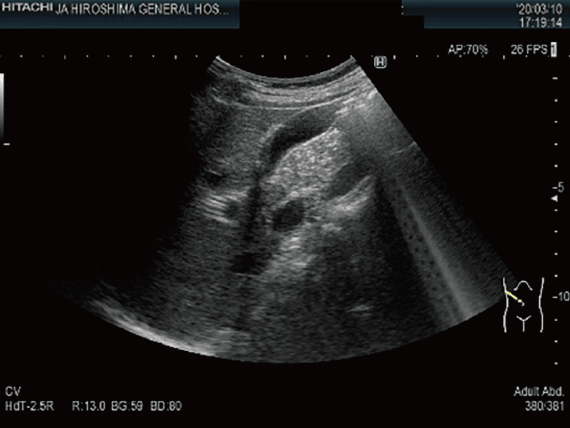

泌尿器超音波検査

腹部と背部より超音波を照射して,腎臓・副腎・膀胱・前立腺などの腹腔内臓器・骨盤内臓器を観察する検査です。各種臓器の腫瘍をはじめとして,結石,嚢胞などの発見や形態の評価に用いられます。